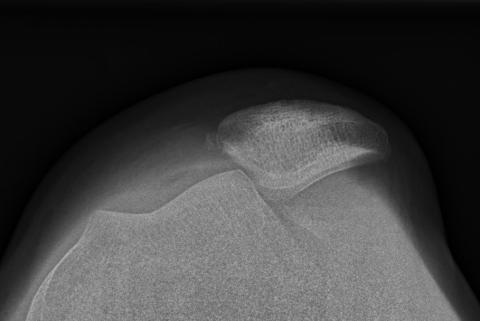

Tangentialoptagelse af et knæ med lateral patellaluksation.

RØNTGENUNDERSØGELSER

Patienter med tegn på akut tilfælde af OPI skal altid have taget røntgenbilleder ved den initiale kontakt. Røntgenundersøgelse efter en lateral patellaluksation skal indbefatte et anterior-posterior-billede, en lateral optagelse af knæet samt en tangentialoptagelse af patella [1]. Ved disse er det muligt at finde evt. osteokondral fraktur, tegn på TD (crossing sign) samt evt. at vurdere patellas højde (patella alta eller baja). Tangentialoptagelsen tages primært for at udelukke osteokondral fraktur, som kan være vanskelig at erkende på AP- og lateraloptagelse. Tangentialoptagelsen af patellofemoralleddet viser ved rutineoptagelser som oftest ikke den proksimale del af trochlea og har derfor begrænset værdi i diagnosticeringen af TD. For at man kan erkende crossing sign, skal det laterale røntgenbillede tages lige (true lateral), dvs. at de posteriore femurkondyler skal være overlejrede (Figur 2).